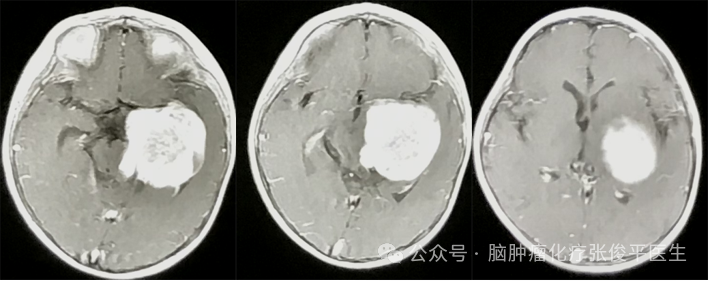

病史描述患兒,男性,8歲。2023年9月患兒右側(cè)臀部偶有疼痛,就診于當(dāng)?shù)蒯t(yī)院按“肌肉拉傷”治療后癥狀加重。后行脊髓核磁提示:脊髓內(nèi)占位。2024年1月初行脊髓手術(shù)治療,術(shù)后病理報(bào)告示:(脊髓)神經(jīng)上皮來(lái)源腫瘤,符合高級(jí)別彌漫性膠質(zhì)瘤,CNSWH04級(jí)?;熯^程術(shù)后1個(gè)月患兒就診我科(首都醫(yī)科大學(xué)三博腦科醫(yī)院神經(jīng)腫瘤化療科),就診時(shí)患兒大小便失禁、持續(xù)頭痛、頭暈,進(jìn)食量少。2024-02-28頭部MRI:雙側(cè)小腦半球、橋小腦角池、鞍上池及雙外側(cè)裂多發(fā)占位病變(下圖)。2024-03-01脊髓核磁提示:延髓、頸、胸、腰髓椎管內(nèi)多發(fā)異常強(qiáng)化,考慮播散轉(zhuǎn)移(下圖)。2024年3月開始于我科行化療聯(lián)合抗血管靶向治療?;?周期后,2024-05-11核磁:頭部、脊髓核磁播散病灶明顯較少(下圖)。大小便失禁癥狀明顯改善,頭痛、頭暈癥狀消失。化療4周期后,2024-07-24核磁:頭部未見明確播散病灶,僅胸腰椎剩余少量異常播散病灶(下圖)。目前,患兒在繼續(xù)治療中。專家點(diǎn)評(píng)兒童高級(jí)別膠質(zhì)瘤有效藥物少,預(yù)后差,尤其是對(duì)于廣泛播散的腫瘤。本例患者為難治性腦脊膜廣泛播散的高級(jí)別膠質(zhì)瘤,無(wú)法通過手術(shù)全切,幸運(yùn)的是,經(jīng)過我科化療聯(lián)合抗血管靶向藥物治療后,腫瘤基本全消,癥狀明顯改善。目前,首都醫(yī)科大學(xué)三博腦科醫(yī)院神經(jīng)腫瘤化療科關(guān)于高級(jí)別膠質(zhì)瘤的臨床試驗(yàn)正在開展中。